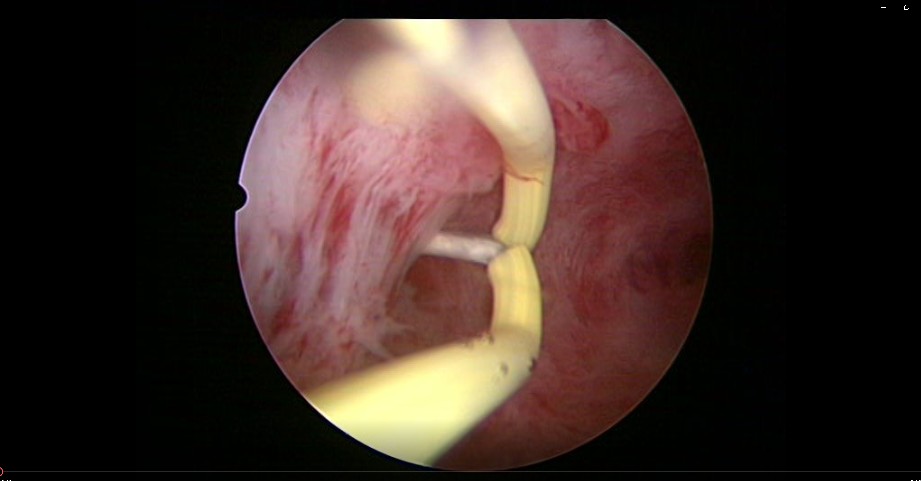

患者32岁,G6P0,继发不孕,2017年8月行宫腔镜探查,发现宫腔两侧及宫底致密粘连,尤其是宫腔右侧多重粘连,宫腔狭小。单极电切分粘,恢复宫腔形态,显露双侧输卵管开口。2018年8月自然妊娠40多天,我在兰州大学附一院生殖中心进修,病人微信发B超给我,大孕囊,胎心微弱,外院疑诊胚胎停育,拟行清宫,嘱病人不要轻易清宫,继续保胎1周,复查B超,胚胎发育正常。病人的信心和坚持成就了她自己和孩子的奇迹,孕期顺利,足月分娩。后病人再次妊娠1次,人流终止妊娠,现41岁,G8P1。